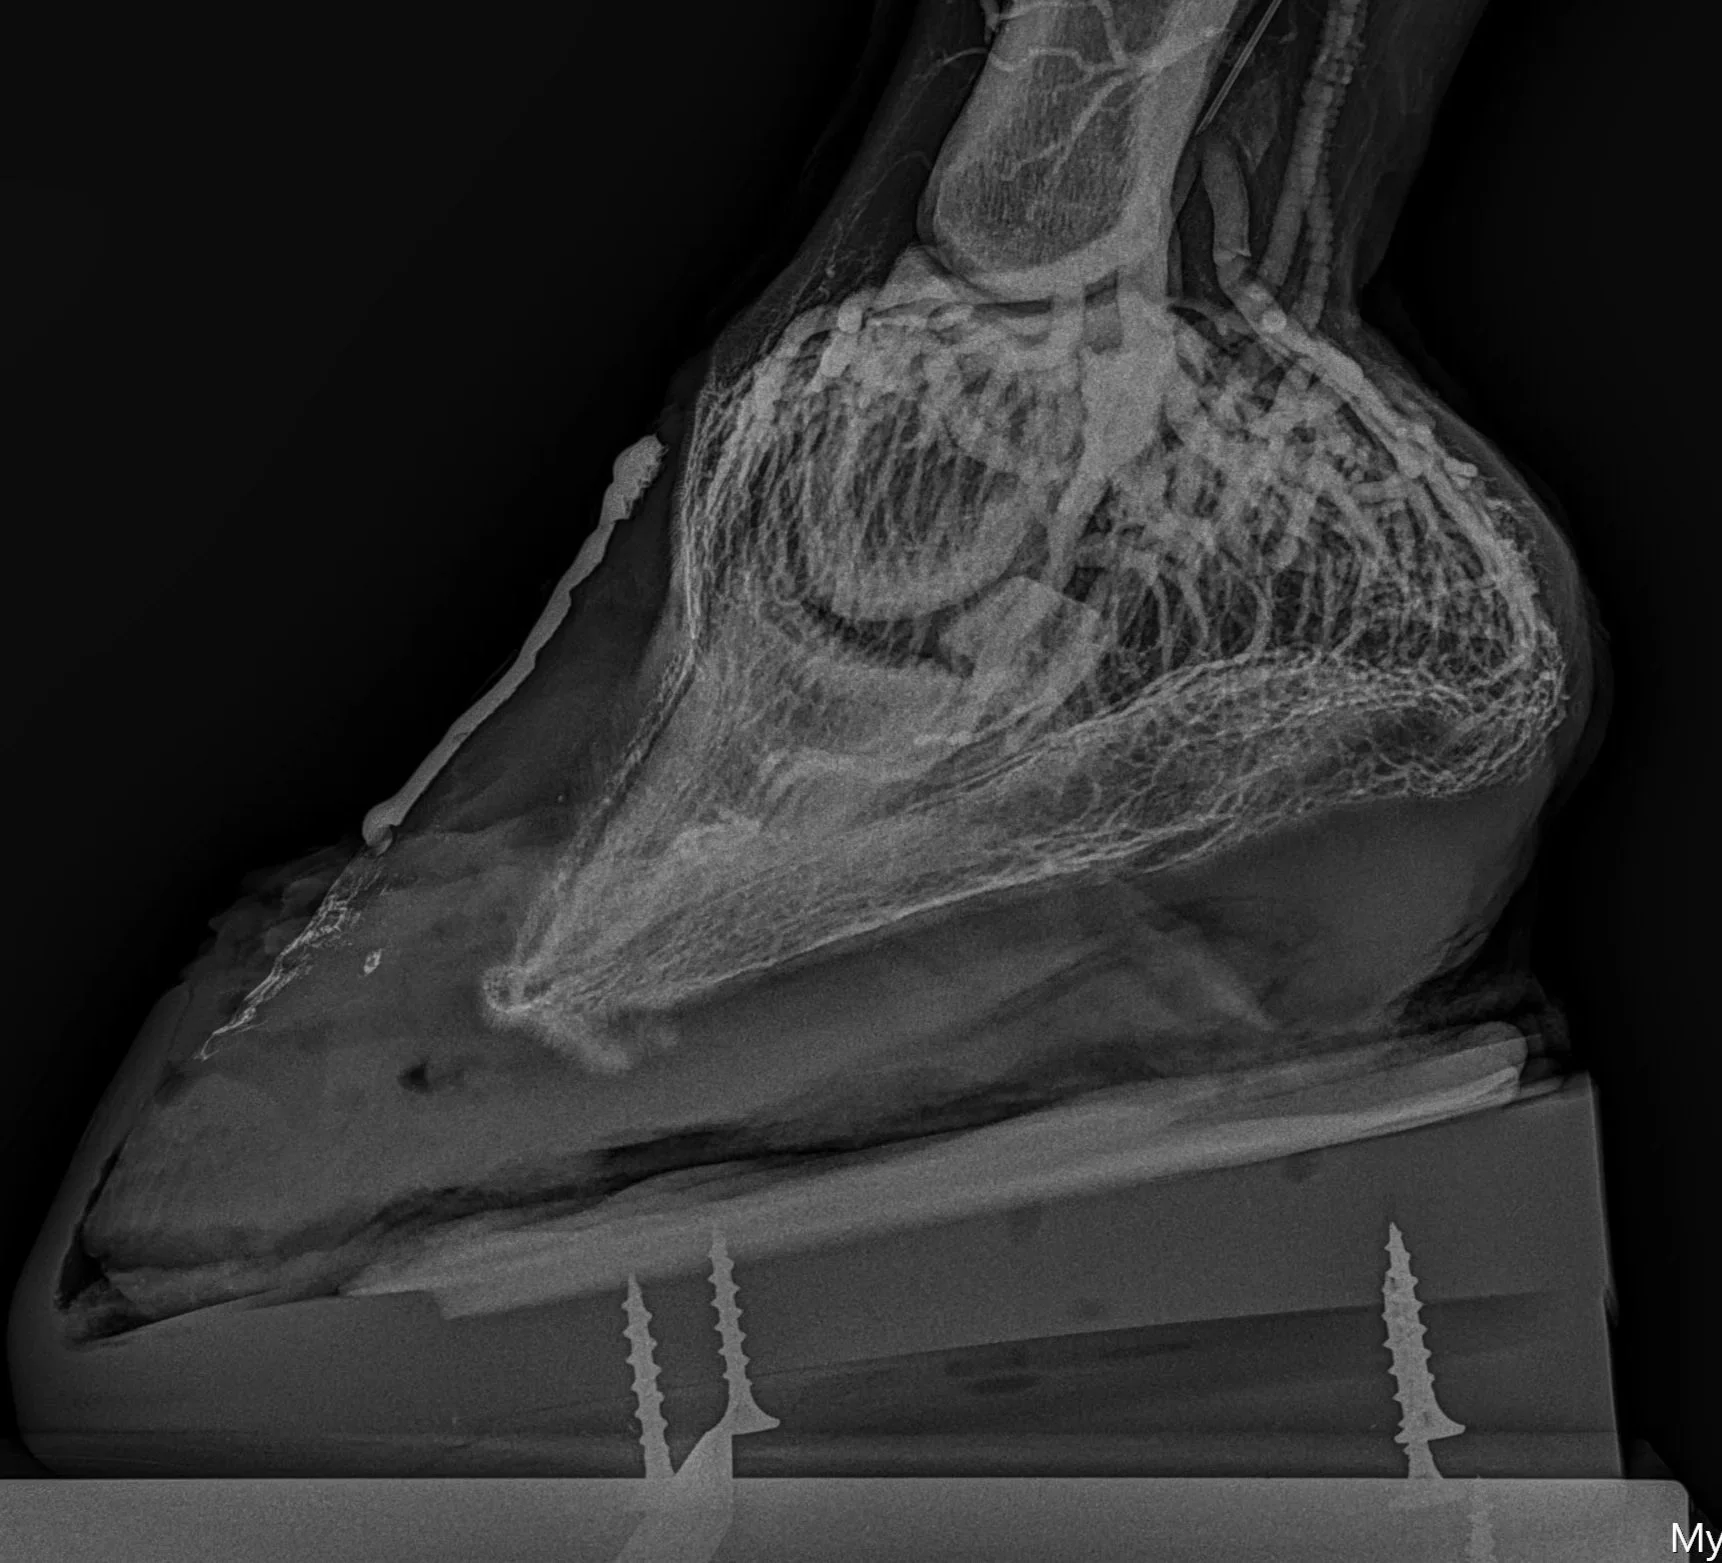

Dr. Kirby Penttila has developed a particular interest in podiatry and has spent the last several years integrating new techniques in imaging to allow adjustments to the biomechanics of the foot in order to improve comfort in horses with many challenging disorders affecting the foot.  These techniques have proven to be very helpful for horses with laminitis, underrun heels, osteoarthritis of the distal and proximal interphalangeal joints, club feet, and caudal heel pain.  Imaging techniques offered include interpretation of low-beam podiatry radiographs and incorporation of venograms into case management of patients affected with laminitis.  Depending on the condition affecting the horse, shoeing options include modified ultimates, rocker rail shoes, full rocker motion shoes, positive pressure frog support, or traditional farriery methods incorporating various shoes and pads.  We work cooperatively with many farriers in the area, but Kirk Shaw of Equine Unlimited plays an important role in jointly formulating and implementing a treatment plan for most of our more challenging cases.  Please don't hesitate to call if you'd like to discuss a particular case that you feel might benefit from expertise in this field.

Laminitis Venogram.jpg